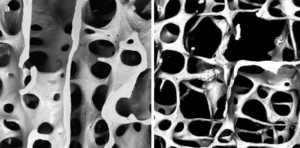

Healthy bones depend on a perfect balance between this demolition and construction. Osteoporosis happens when this balance is lost. Demolition (resorption) happens faster than building (formation), making bones weak and porous. Emerging evidence suggests microplastics severely disrupt this balance.

Young animals exposed to microplastics experienced stunted growth and skeletal deformities.17The Effects of Microplastics on Musculoskeletal Disorder; A…, accessed October 18, 2025, https://pmc.ncbi.nlm.nih.gov/articles/PMC11775366/ Rodrigo Bueno de Oliveira, lead author of the main review, noted that some studies showed growth stopping entirely.18agencia.fapesp.br, accessed October 18, 2025, https://agencia.fapesp.br/microplastics-may-affect-bone-health/55881#:~:text=For%20example%2C%20in%20vitro%20studies,in%20Nephrology%20(LEMON)%20at%20the Advanced scans (micro-CT) revealed damage inside the bones of adult mice. Their bone microstructure looked destroyed, with fewer internal supports (trabeculae) and less overall bone mass, similar to osteoporosis. Blood tests also showed disrupted levels of calcium and phosphorus, key minerals for bone health. Some studies even found lower white blood cell counts, suggesting damage to the bone marrow itself.19Effects of microplastics on the bones: a comprehensive review – ResearchGate, accessed October 18, 2025, https://www.researchgate.net/publication/392969735_Effects_of_microplastics_on_the_bones_a_comprehensive_review

Microscopic comparison of bone structure. (a) Normal, dense trabecular bone. (b) Osteoporotic bone showing thinner, less connected trabeculae and larger pores. Credit: ResearchGate.